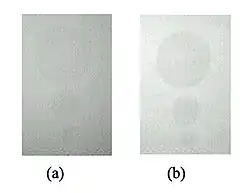

- The reduction in contrast due to scatter can be appreciated from the images in Figure 3.16. Here, two radiographs are seen of three small, thin and circular plastic disks, which are intended to mimic subtle lesions in images. The image in panel (a) was acquired with a level of scatter representative of clinical imaging conditions. The image in panel (b) was generated using a computerized scatter reduction method which reduced the scatter to about a third. It is clear from the figure that scatter can greatly reduce image contrast to the extent that subtle opacities may not be visualized.